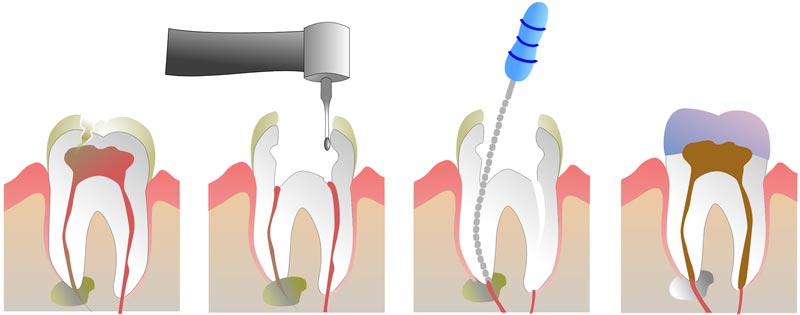

درمان ریشه یا عصبکشی یکی از مهمترین و مؤثرترین روشها برای ترمیم ریشه دندان آسیبدیده است. در این درمان، متخصص دندانپزشک ابتدا با استفاده از ابزارهای خاص، پالپ آسیب دیده را از دندان خارج کرده و فضای داخلی آن را تمیز میکند. سپس این فضای خالی با مواد پرکنندهای مانند گوتاپرکا پر میشود که میتواند به حفظ دندان کمک کند و از عفونت جلوگیری نماید. این فرآیند معمولاً در یک یا چند جلسه انجام میشود و پس از اتمام، دندان به صورت کاملاً سالم و بدون درد در دهان باقی میماند.

در درمان ریشه دندان، دندانپزشک ابتدا پالپ عفونی شده را خارج کرده و کانالهای ریشه دندان را تمیز و ضدعفونی میکند. سپس، کانالها را با مواد خاص پر میکند تا از بروز عفونتهای جدید جلوگیری شود. این درمان میتواند عفونت را درمان کرده و دندان را از آسیبهای جدیتری همچون از دست دادن دندان نجات دهد. در صورتی که درمان ریشه بهطور صحیح انجام شود و پیگیریهای لازم صورت گیرد، دندان ممکن است برای سالها سالم باقی بماند.